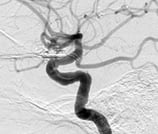

Angiografia projeção frontal evidenciando um aneurisma cerebral.

Angiografia projeção frontal mostrando o aneurisma cerebral (círculo).